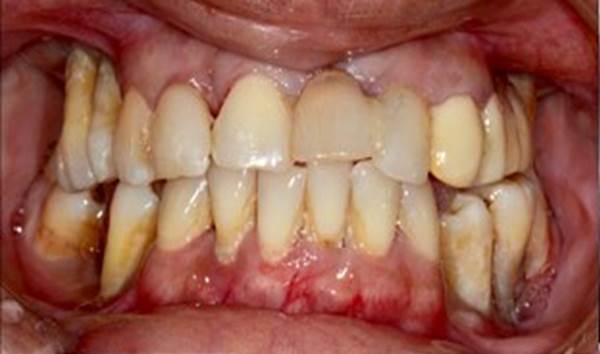

Clinical case: AFull transition from natural teeth to all-on-6 bridges

with AnyRidge implants

- Courtesy of Dr. Rabih Abi Nader, UAE -

Keywords

Full-mouth rehabilitation, minimal layering, Zirconia, all-on-6, life changing result, edentulous ,Dr. Rabih Abi Nader, AnyRidge

Products:

AnyRidge implant system

“AnyRidge shows excellent esthetic results

with Zirconia prosthesis in full-mouth rehabilitation case . ”